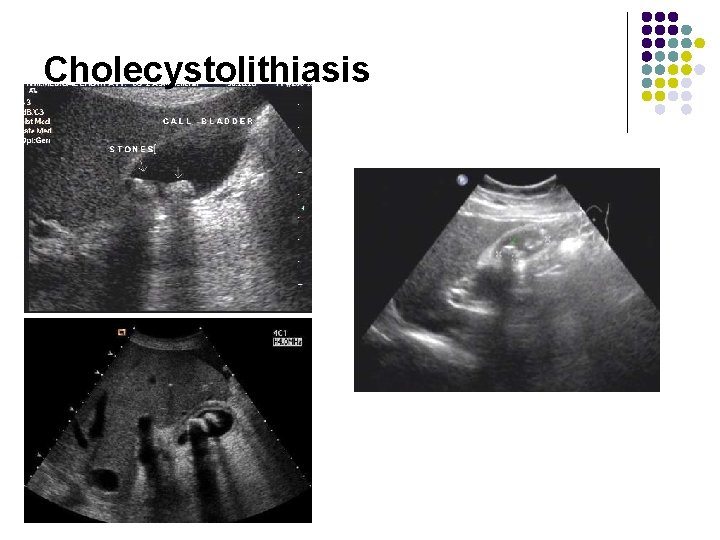

Cholecystolithiasis • Gallstone with shadowing: high-level intraluminal echoes+ acoustic shadowing(100%diagnostic) • Mobility of the stone by moving the patient during ultrasound scanning

Cholecystolithiasis Gallstone with shadowing: high-level intraluminal echoes+ acoustic shadowing(100%diagnostic) Mobility of the stone by moving the patient during ultrasound scanning